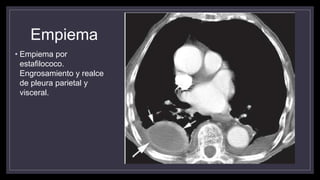

• Empiema por

estafilococo.

Engrosamiento y realce

de pleura parietal y

visceral.